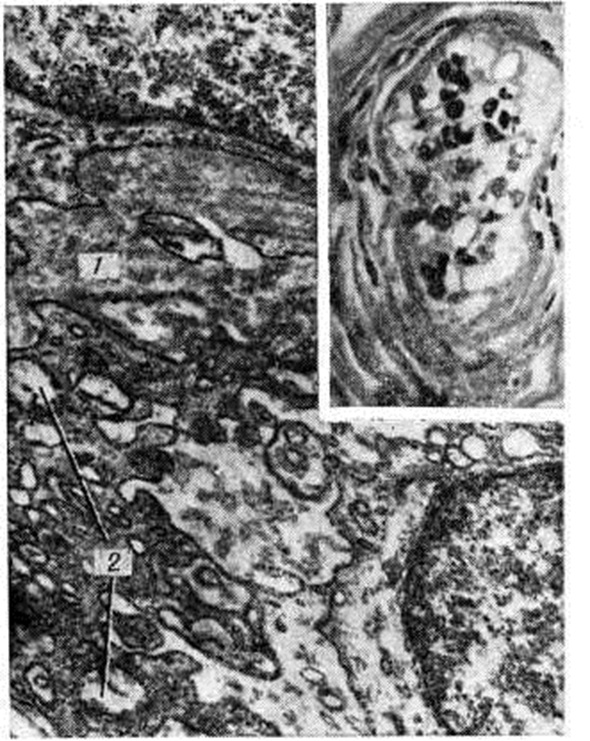

Гиалиноз наблюдается в соединительной ткани, строме органов и стенке сосудов (рисунок 2) в исходе плазматического пропитывания, фибриноидного набухания, склероза, хронический воспаления, некроза. В исходе плазматического пропитывания возникает Гиалиноз сосудов, чаще в артериальной системе. Наиболее распространён Гиалиноз мелких артерий и артериол (смотри Артериолосклероз). Гиалиноз артериол возникает в результате повреждения эндотелия, аргирофильных мембран и гладкомышечных волокон и пропитывания стенок сосуда белками плазмы крови, которые затем подвергаются ферментативным воздействиям, коагулируются и уплотняются, превращаясь в гиалиноподобное плотное вещество. Гиалиновые массы оттесняют кнаружи и разрушают эластическую пластинку, что ведёт к истончению средней оболочки; в результате артериолы превращаются в утолщённые плотные трубочки с резко суженным или полностью закрытым просветом. Гиалиноз мелких артерий и артериол, носящий системный характер, но наиболее выраженный в почках (рисунок 3 и 4), головном мозге, сетчатке глаза, поджелудочной железе, коже (рисунок 5), особенно характерен для гипертонической болезни (гипертонический артериологиалиноз). Нередко системный Гиалиноз артериол и мелких артерий наблюдается при хронический васкулярном гломерулонефрите и симптоматической артериальной гипертензии любого генеза. Распространённый Гиалиноз артерий эластического и эластическо-мышечного типов постоянно наблюдается при атеросклерозе, диабете и отражает процессы плазморрагии и инсудации, характерные для этих заболеваний. Местный Гиалиноз артерий как физиологическое явление встречается в селезёнке взрослых и пожилых людей, отражая функционально-морфологически особенности селезёнки как органа депонирования крови.

В исходе фибриноидного набухания, ведущего к деструкции коллагена и пропитыванию ткани плазменными белками и полисахаридами, соединительнотканные пучки разбухают, теряют фибриллярность и сливаются в однородную плотную хрящеподобную массу; клеточные элементы сдавливаются и подвергаются атрофии. Подобный механизм развития Гиалиноз собственно соединительной ткани и сосудистой стенки особенно часто наблюдается при заболеваниях с иммунными нарушениями. Так, системный Гиалиноз соединительной ткани и стенок сосудов выражен при коллагеновых болезнях: Гиалиноз клапанов сердца, стромы миокарда — при ревматизме, Гиалиноз синовиальных оболочек — при ревматоидном артрите, Гиалиноз кожи — при склеродермии, Гиалиноз стенок сосудов — при узелковом артериите и системной красной волчанке. Таков же механизм распространённого Гиалиноз почечных клубочков при иммунокомплексном гломерулонефрите. В этих случаях гиалин строится на иммунных комплексах, что подтверждает роль иммунологический механизмов в развитии Гиалиноз. Местный Гиалиноз может завершать фибриноидные изменения в дне хронический язвы желудка, в ткани червеобразного отростка при аппендиците, а также в очаге хронический воспаления.